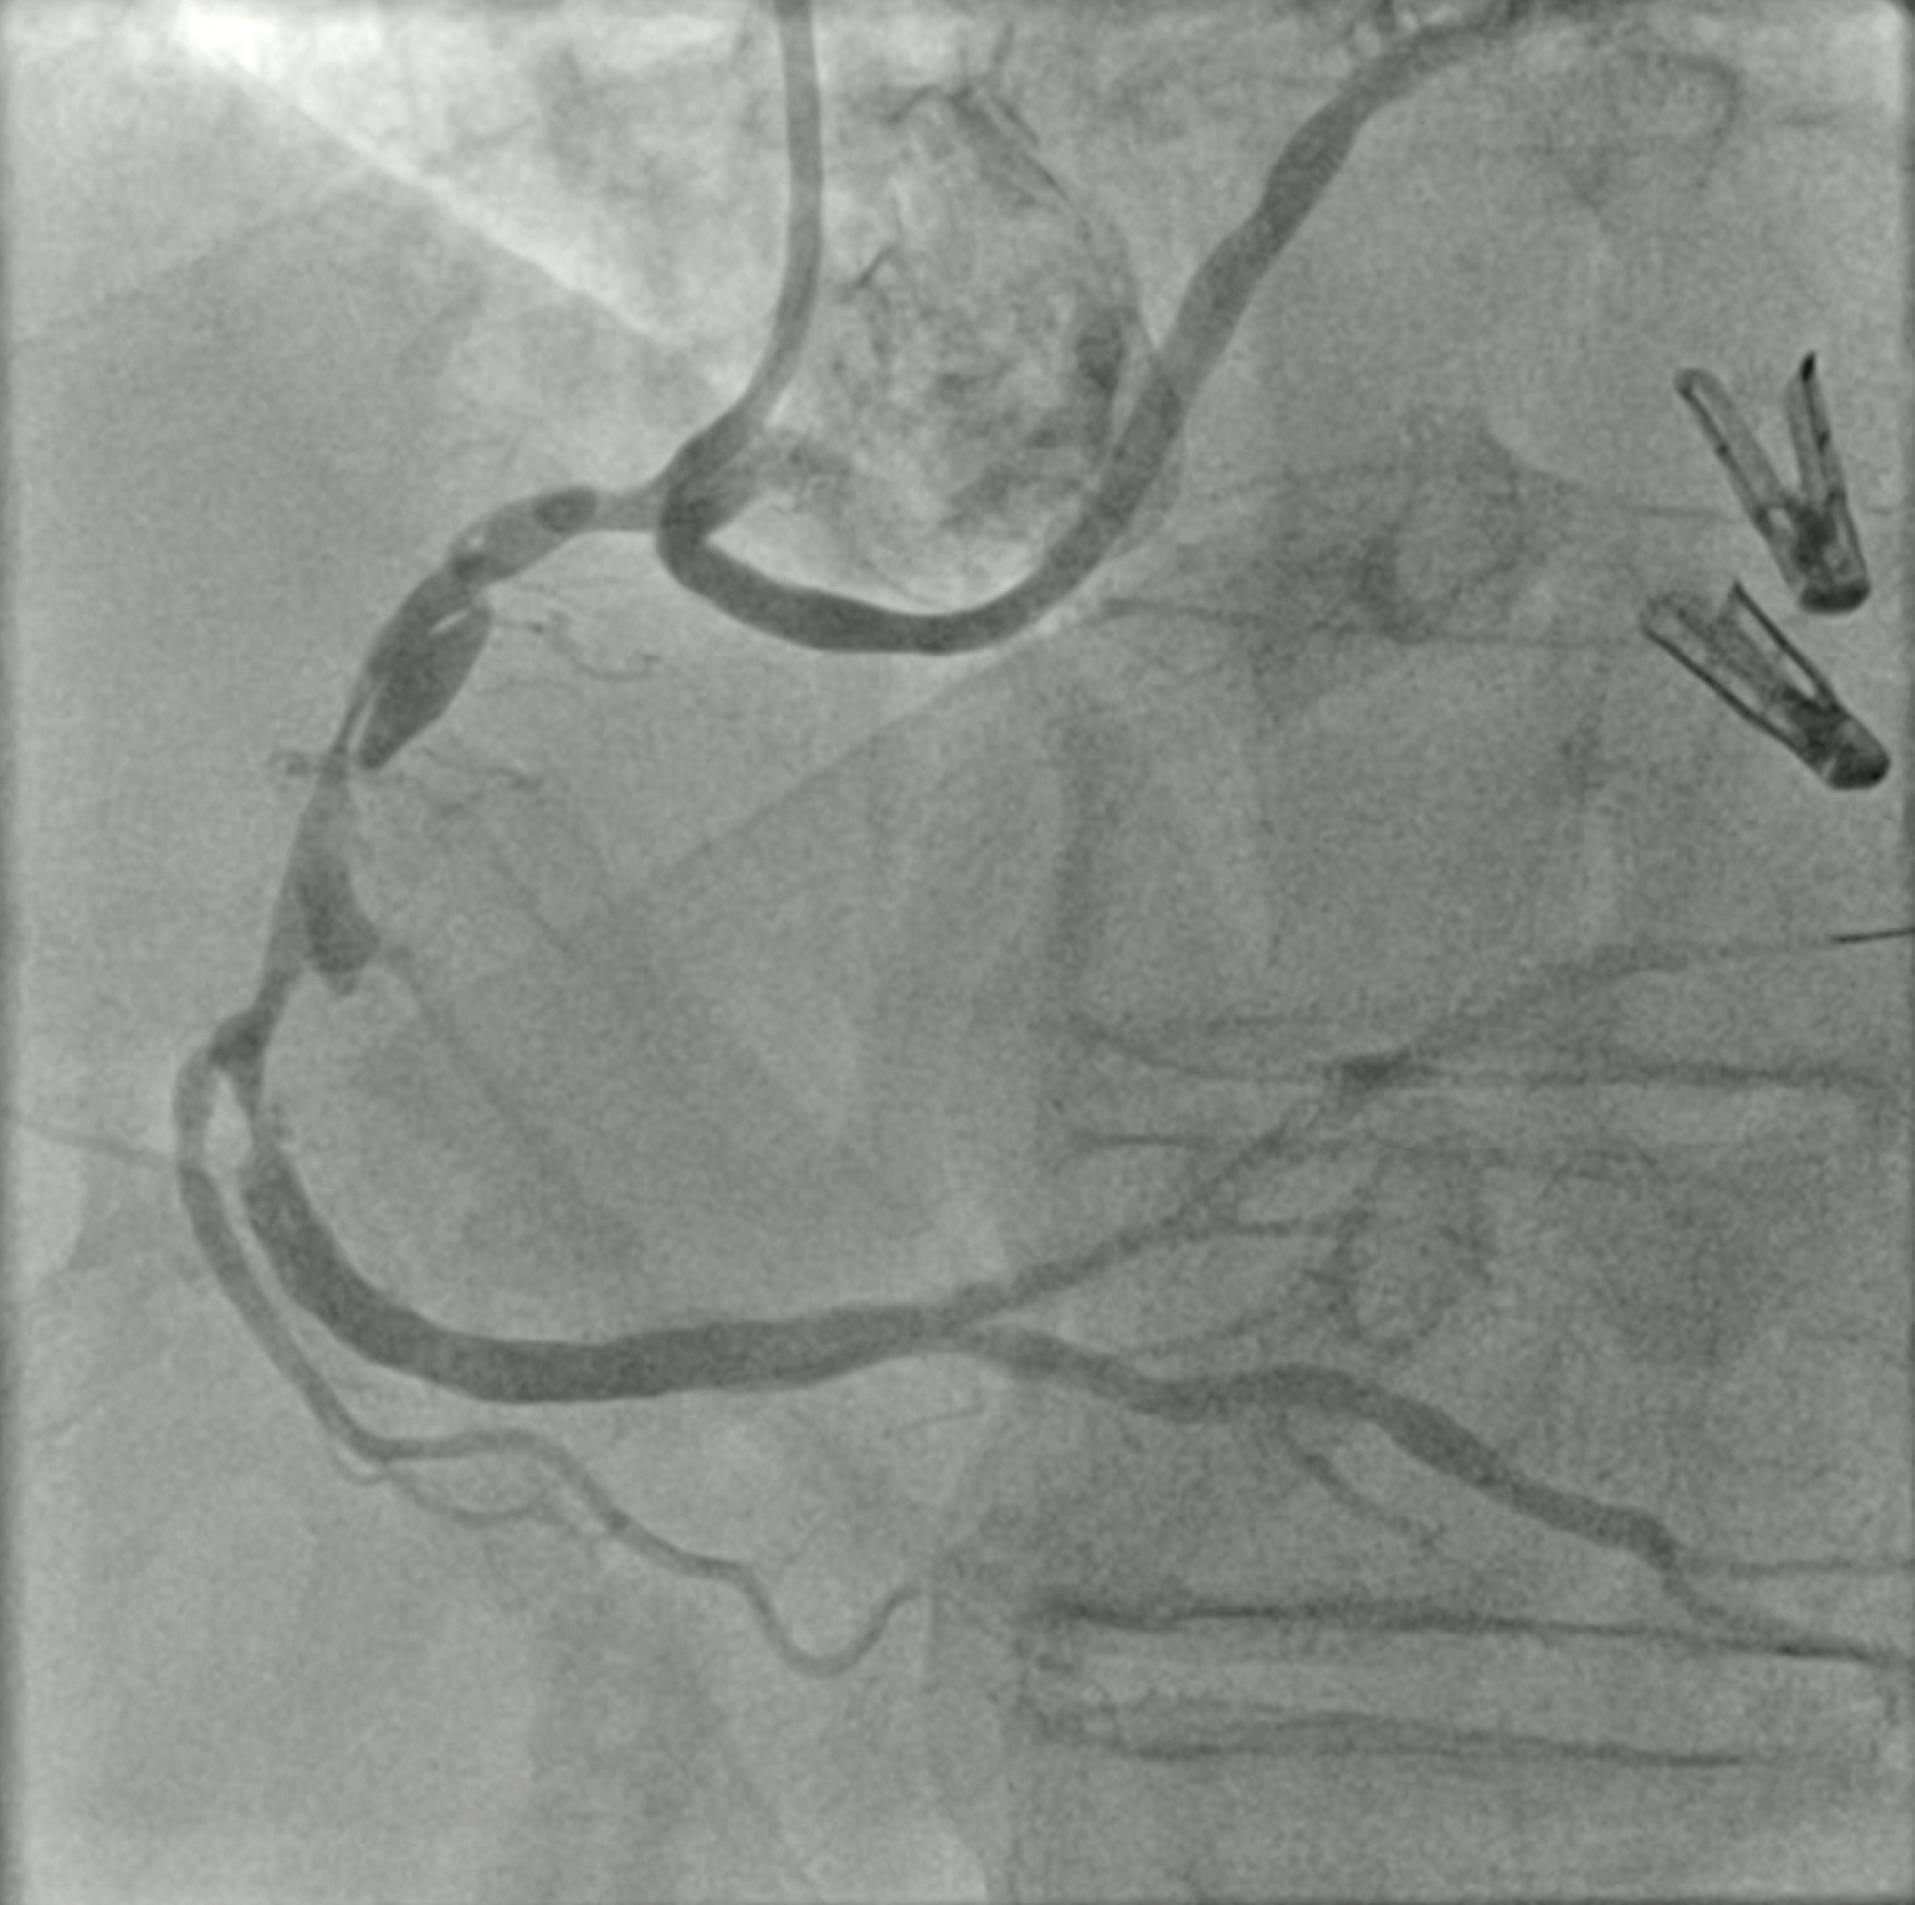

A male in his mid-60s, an ex-smoker and with type 2 diabetes mellitus, presented to the emergency department with a 2-hour history of de novo typical chest pain at rest. The 12-lead electrocardiogram showed an anterior STEMI. The patient was transferred to the catheterization laboratory for primary PCI after receiving intravenous loading doses of aspirin (250 mg) and unfractionated heparin (5,000 IU). The coronary angiogram demonstrated an acute thrombotic occlusion of the proximal LAD with high thrombus burden (TIMI thrombus grade 5) (Figure 1).

Figure 1. Coronary angiogram showing an acute thrombotic occlusion of the proximal LAD with a high thrombus burden.